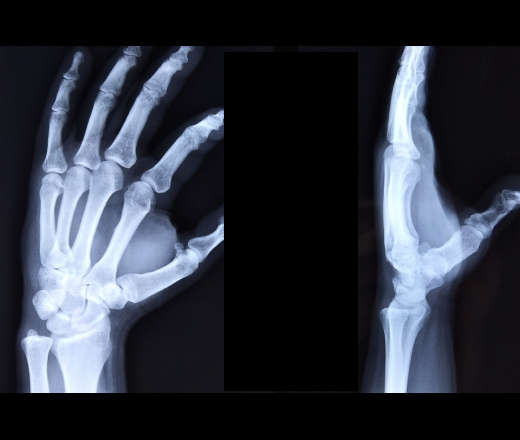

Пол пациента: Мужской пол Тип патологии: Другое Область исследования: Скелетно-мышечная система Методы исследования: Rg Мужчина 35л, травма на тренировке. Перелом 5 пястной кости? кисть ID:83234 Цель публикации: Консультация Mon, 21/10/2019 - 17:02 #1 И.Бондаренко Offline Last seen: 3 days 5 hours ago Joined: 13.09.2011 - 22:55 Posts: 9206 Интересный перелом. Сказал бы , что невиданный. Боксёр что ли? Почти все пястные были сломаны. Наверное очередь соблюдается Wed, 23/10/2019 - 19:13 #2 atexta Offline Last seen: 2 years 11 months ago Joined: 08.02.2014 - 18:41 Posts: 4842 Спасибо, Игорь, а у меня вот закрались сомнения ( . Жаль что больше никто не высказался ( Приложения: Не нам судить… Wed, 23/10/2019 - 19:25 #3 NIL Offline Last seen: 2 weeks 4 days ago Joined: 25.11.2013 - 20:50 Posts: 18208 atexta wrote: ... у меня вот закрались сомнения У меня по поводу свежего перелома тоже большие сомнения. "Слушай всех, прислушивайся к немногим, решай сам".© Wed, 23/10/2019 - 19:27 #4 atexta Offline Last seen: 2 years 11 months ago Joined: 08.02.2014 - 18:41 Posts: 4842 NIL wrote: atexta wrote: ... у меня вот закрались сомнения У меня по поводу свежего перелома тоже большие сомнения. Спасибо 👭 Не нам судить…

Интересный перелом. Сказал бы , что невиданный. Боксёр что ли? Почти все пястные были сломаны. Наверное очередь соблюдается